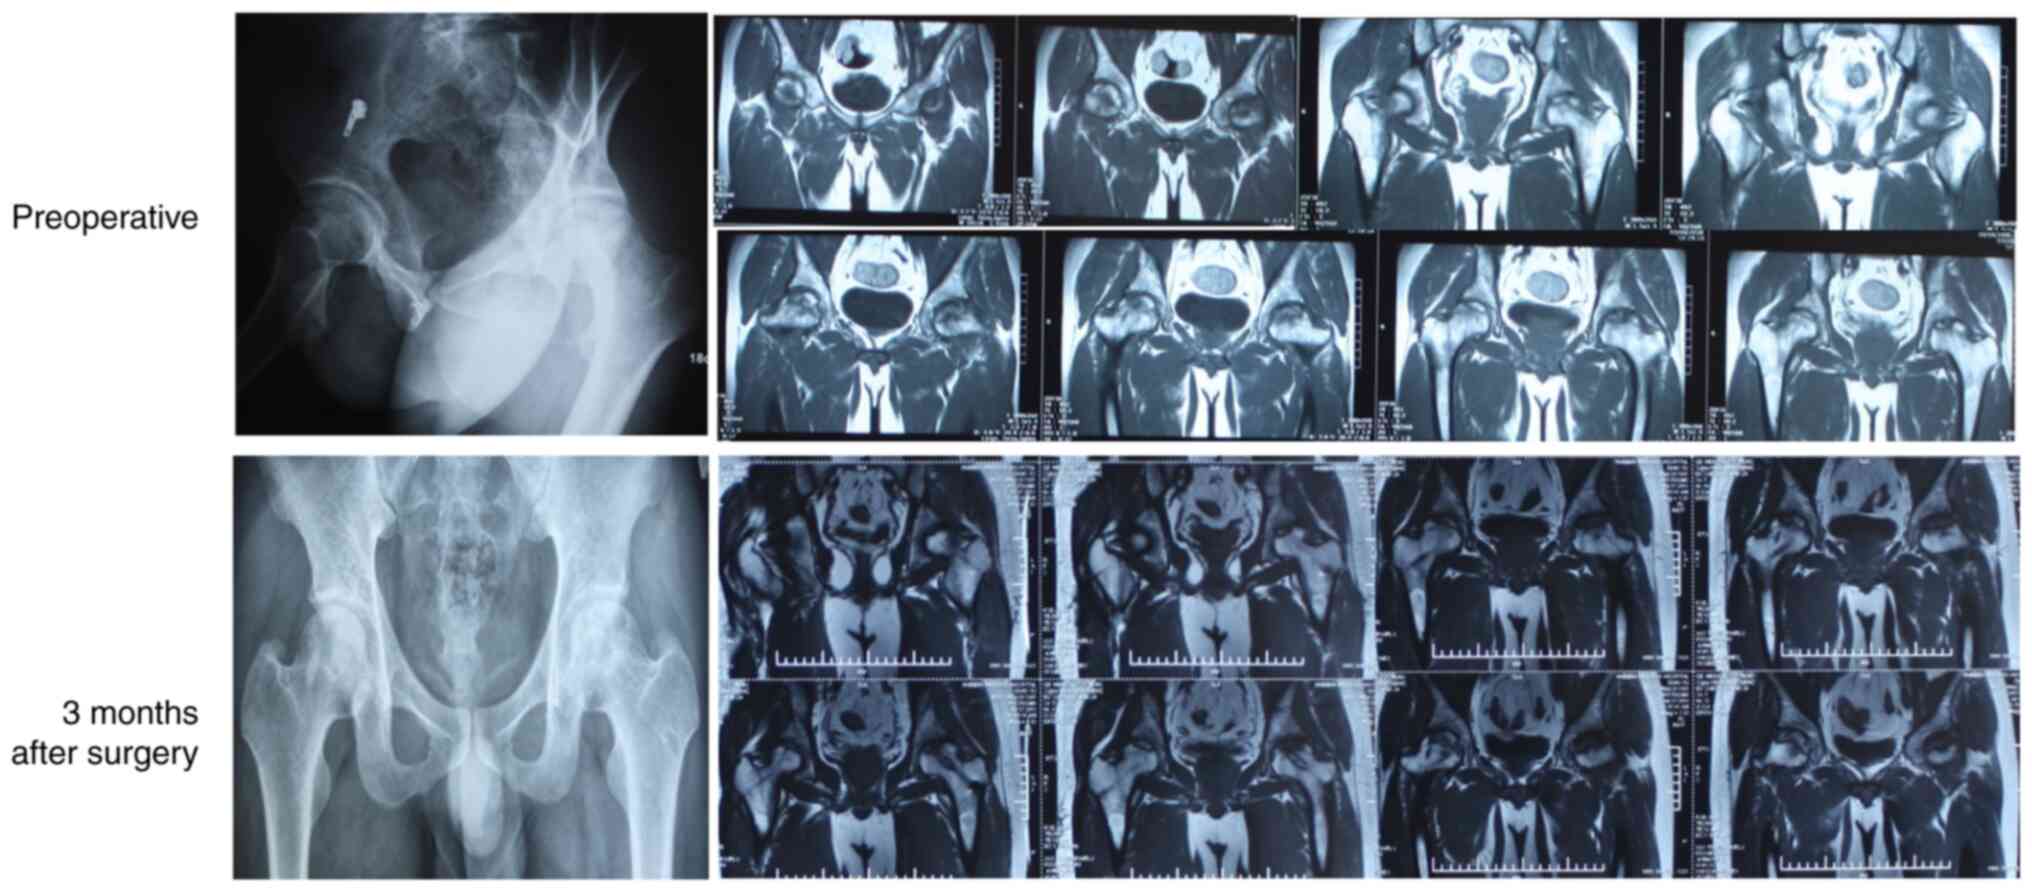

CD

CD is the commonest surgical procedure for early-stage osteonecrosis and is used to relieve pain and promote bone regeneration and repair (67,68). As shown in Fig. 2, pure CD can repair and delay the progression of NONFH (67) by reducing intramedullary pressure on the inside of the femoral head, accelerating bone regeneration, reversing femoral head necrosis and improving blood flow. However, the clinical results so far are inconclusive and indicate that CD may have an improved effect on early-stage ONFH (68).

Figure 2

Typical imaging results of non-traumatic osteonecrosis of the femoral head after pure core decompression.